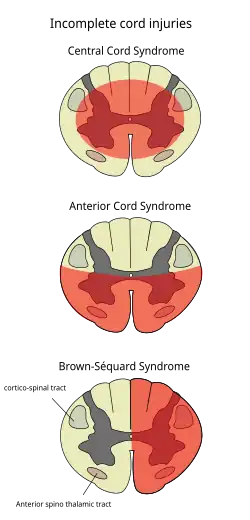

Central cord syndrome

Central cord syndrome, almost always resulting from damage to the cervical spinal cord, is characterized by weakness in the arms with relative sparing of the legs, and spared sensation in regions served by the sacral segments.[25] There is loss of sensation of pain, temperature, light touch, and pressure below the level of injury.[26] The spinal tracts that serve the arms are more affected due to their central location in the spinal cord, while the corticospinal fibers destined for the legs are spared due to their more external location.[26]

The most common of the incomplete SCI syndromes, central cord syndrome usually results from neck hyperextension in older people with spinal stenosis. In younger people, it most commonly results from neck flexion.[27] The most common causes are falls and vehicle accidents; however other possible causes include spinal stenosis and impingement on the spinal cord by a tumor or intervertebral disc.[28]

Anterior spinal artery syndrome

Anterior spinal artery syndrome also known as anterior spinal cord syndrome, due to damage to the front portion of the spinal cord or reduction in the blood supply from the anterior spinal artery, can be caused by fractures or dislocations of vertebrae or herniated disks.[26] Below the level of injury, motor function, pain sensation, and temperature sensation are lost, while sense of touch and proprioception (sense of position in space) remain intact.[29][27] These differences are due to the relative locations of the spinal tracts responsible for each type of function.

Brown-Séquard syndrome

Brown-Séquard syndrome occurs when the spinal cord is injured on one side much more than the other.[30] It is rare for the spinal cord to be truly hemisected (severed on one side), but partial lesions due to penetrating wounds (such as gunshot or knife wounds) or fractured vertebrae or tumors are common.[31] On the ipsilateral side of the injury (same side), the body loses motor function, proprioception, and senses of vibration and touch.[30] On the contralateral (opposite side) of the injury, there is a loss of pain and temperature sensations. If the injury is above pyramidal decussation there is contralateral hemiplegia, at the level of decussation there is completed motor loss on both sides and below pyramidal decussation there is ipsilateral hemiplegia.

[28][30]Spinothalamic tracts are in charge for pain and temperature sensation and because these tracts cross to the opposite side and above the spinal cord there is loss on the contralateral side.[32]